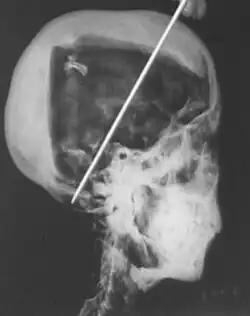

- Na cabeça da múmia de Tao II (aquele da lenda dos hipopótamos) se pode ver os ferimentos recebidos na batalha.